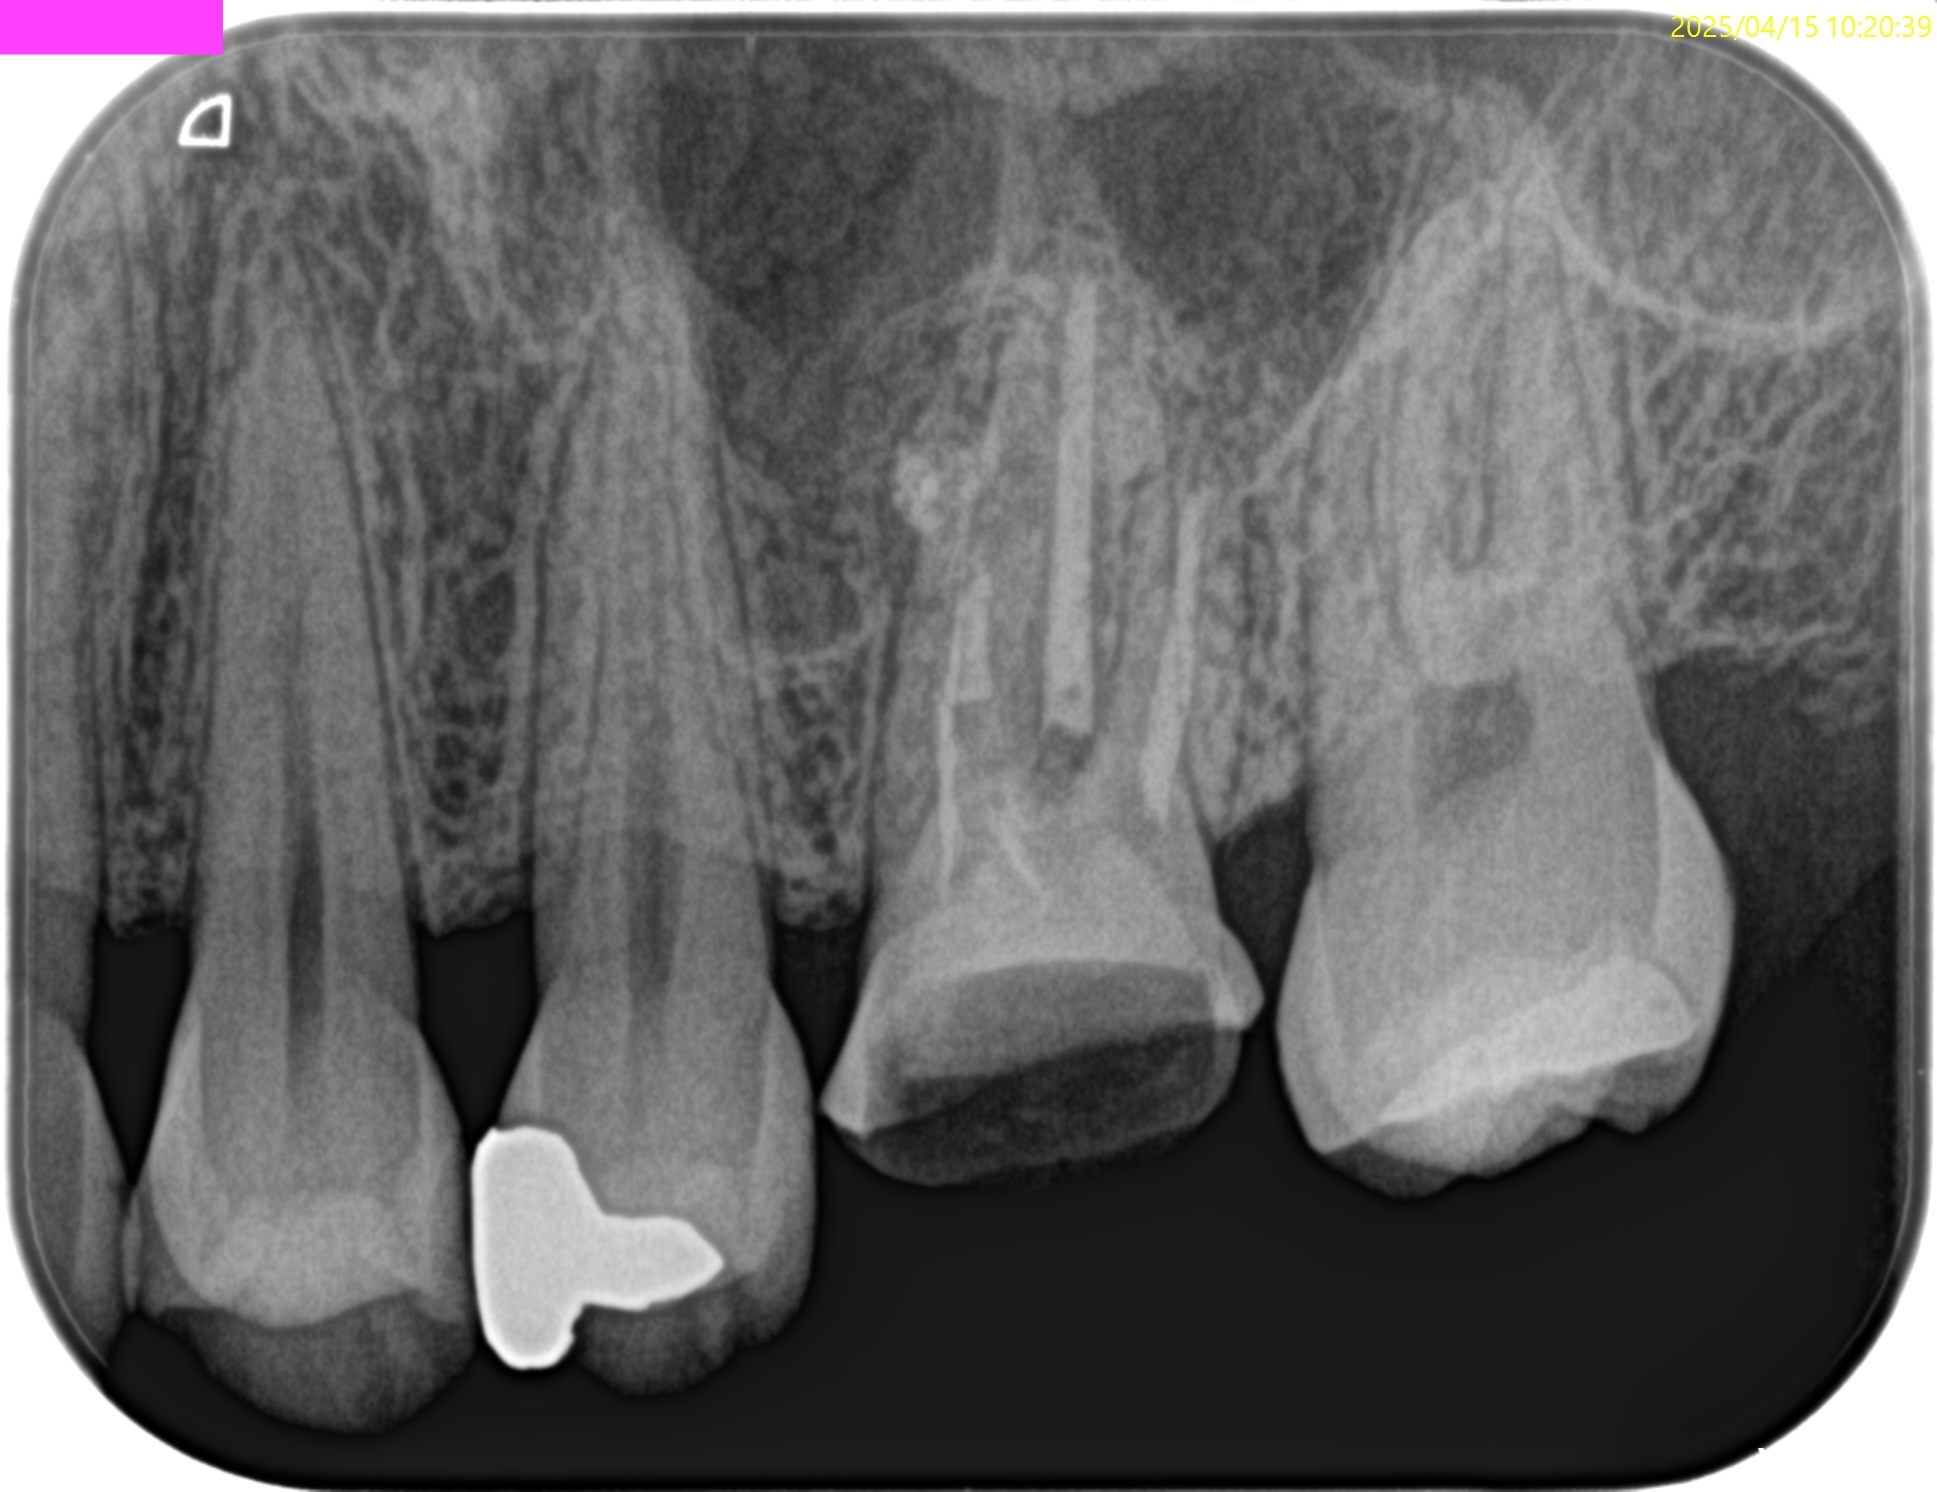

PA(2025.4.15)

MBの根管口の歯質が少ない。

垂直性歯根破折を惹起させるものだ。

歯内療法学的診断(2025.4.15)

Pulp Dx: Previously initiated thrapy

Periapical Dx: Symptomatic apical periodontitis

Recommended Tx: Core build up, Perforation repair→MB Apicoectomy